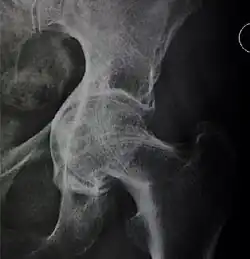

Crowe classification

In 1979 Dr. John F. Crowe et al. proposed a classification to define the degree of malformation and dislocation. Grouped from least severe Crowe I dysplasia to most severe Crowe IV.[13] This classification is very useful for studying treatment results.

Rather than using the Wiberg angle because it makes it difficult to quantify the degree of dislocation they used 3 key elements to determine the degree of subluxation: A reference line at the lower rim of the "teardrop", junction between the femoral head and neck of the respective joint and the height of the pelvis (vertical measurement). They studied anteroposterior pelvic x-rays and drew horizontal lines through the lower rim of a feature called "teardrop". The distance between this line and the middle lines of the junction between femur head and neck gave them a measure of the degree of femur head subluxation. They further established that a "normal" diameter of the femur head measures 20% of the height of the pelvis. If the middle line of the neck-head junction was more than 10% of the pelvis height above the reference line they considered the joint to be more than 50% dislocated.[13]

The following types resulted:[13]

| Class | Description | Dislocation |

|---|---|---|

| Crowe I | Femur and acetabulum show minimal abnormal development. | Less than 50% dislocation |

| Crowe II | The acetabulum shows abnormal development. | 50% to 75% dislocation |

| Crowe III | The acetabula is developed without a roof. A false acetabulum develops opposite the dislocated femur head position. The joint is fully dislocated. | 75% to 100% dislocation |

| Crowe IV | The acetabulum is insufficiently developed. Since the femur is positioned high up on the pelvis this class is also known as "high hip dislocation". | 100% dislocation |